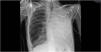

Our patient experienced clinical stagnation for 5 days due to complete atelectasis of the left lung. Non-invasive ventilation was alternated with high flow nasal cannula to maintain saturations at 90%. On the sixth day of clinical stagnation, the first respiratory physiotherapy intervention was performed. A pre- and post-radiological assessment was carried out. The recruitment of the left lung was clearly observed improving not only the radiological control but also the patient's symptoms and gasometric control, achieving PaO2/FiO2 values>300 within 24h. The respiratory physiotherapist's intervention had a significant impact on the patient's health, achieving the predefined goals prior to the session. Following clinical improvement, the patient was able to be transferred to their reference hospital within the next 48h, shortening their stay in the ICU (Figs. 1 and 2).